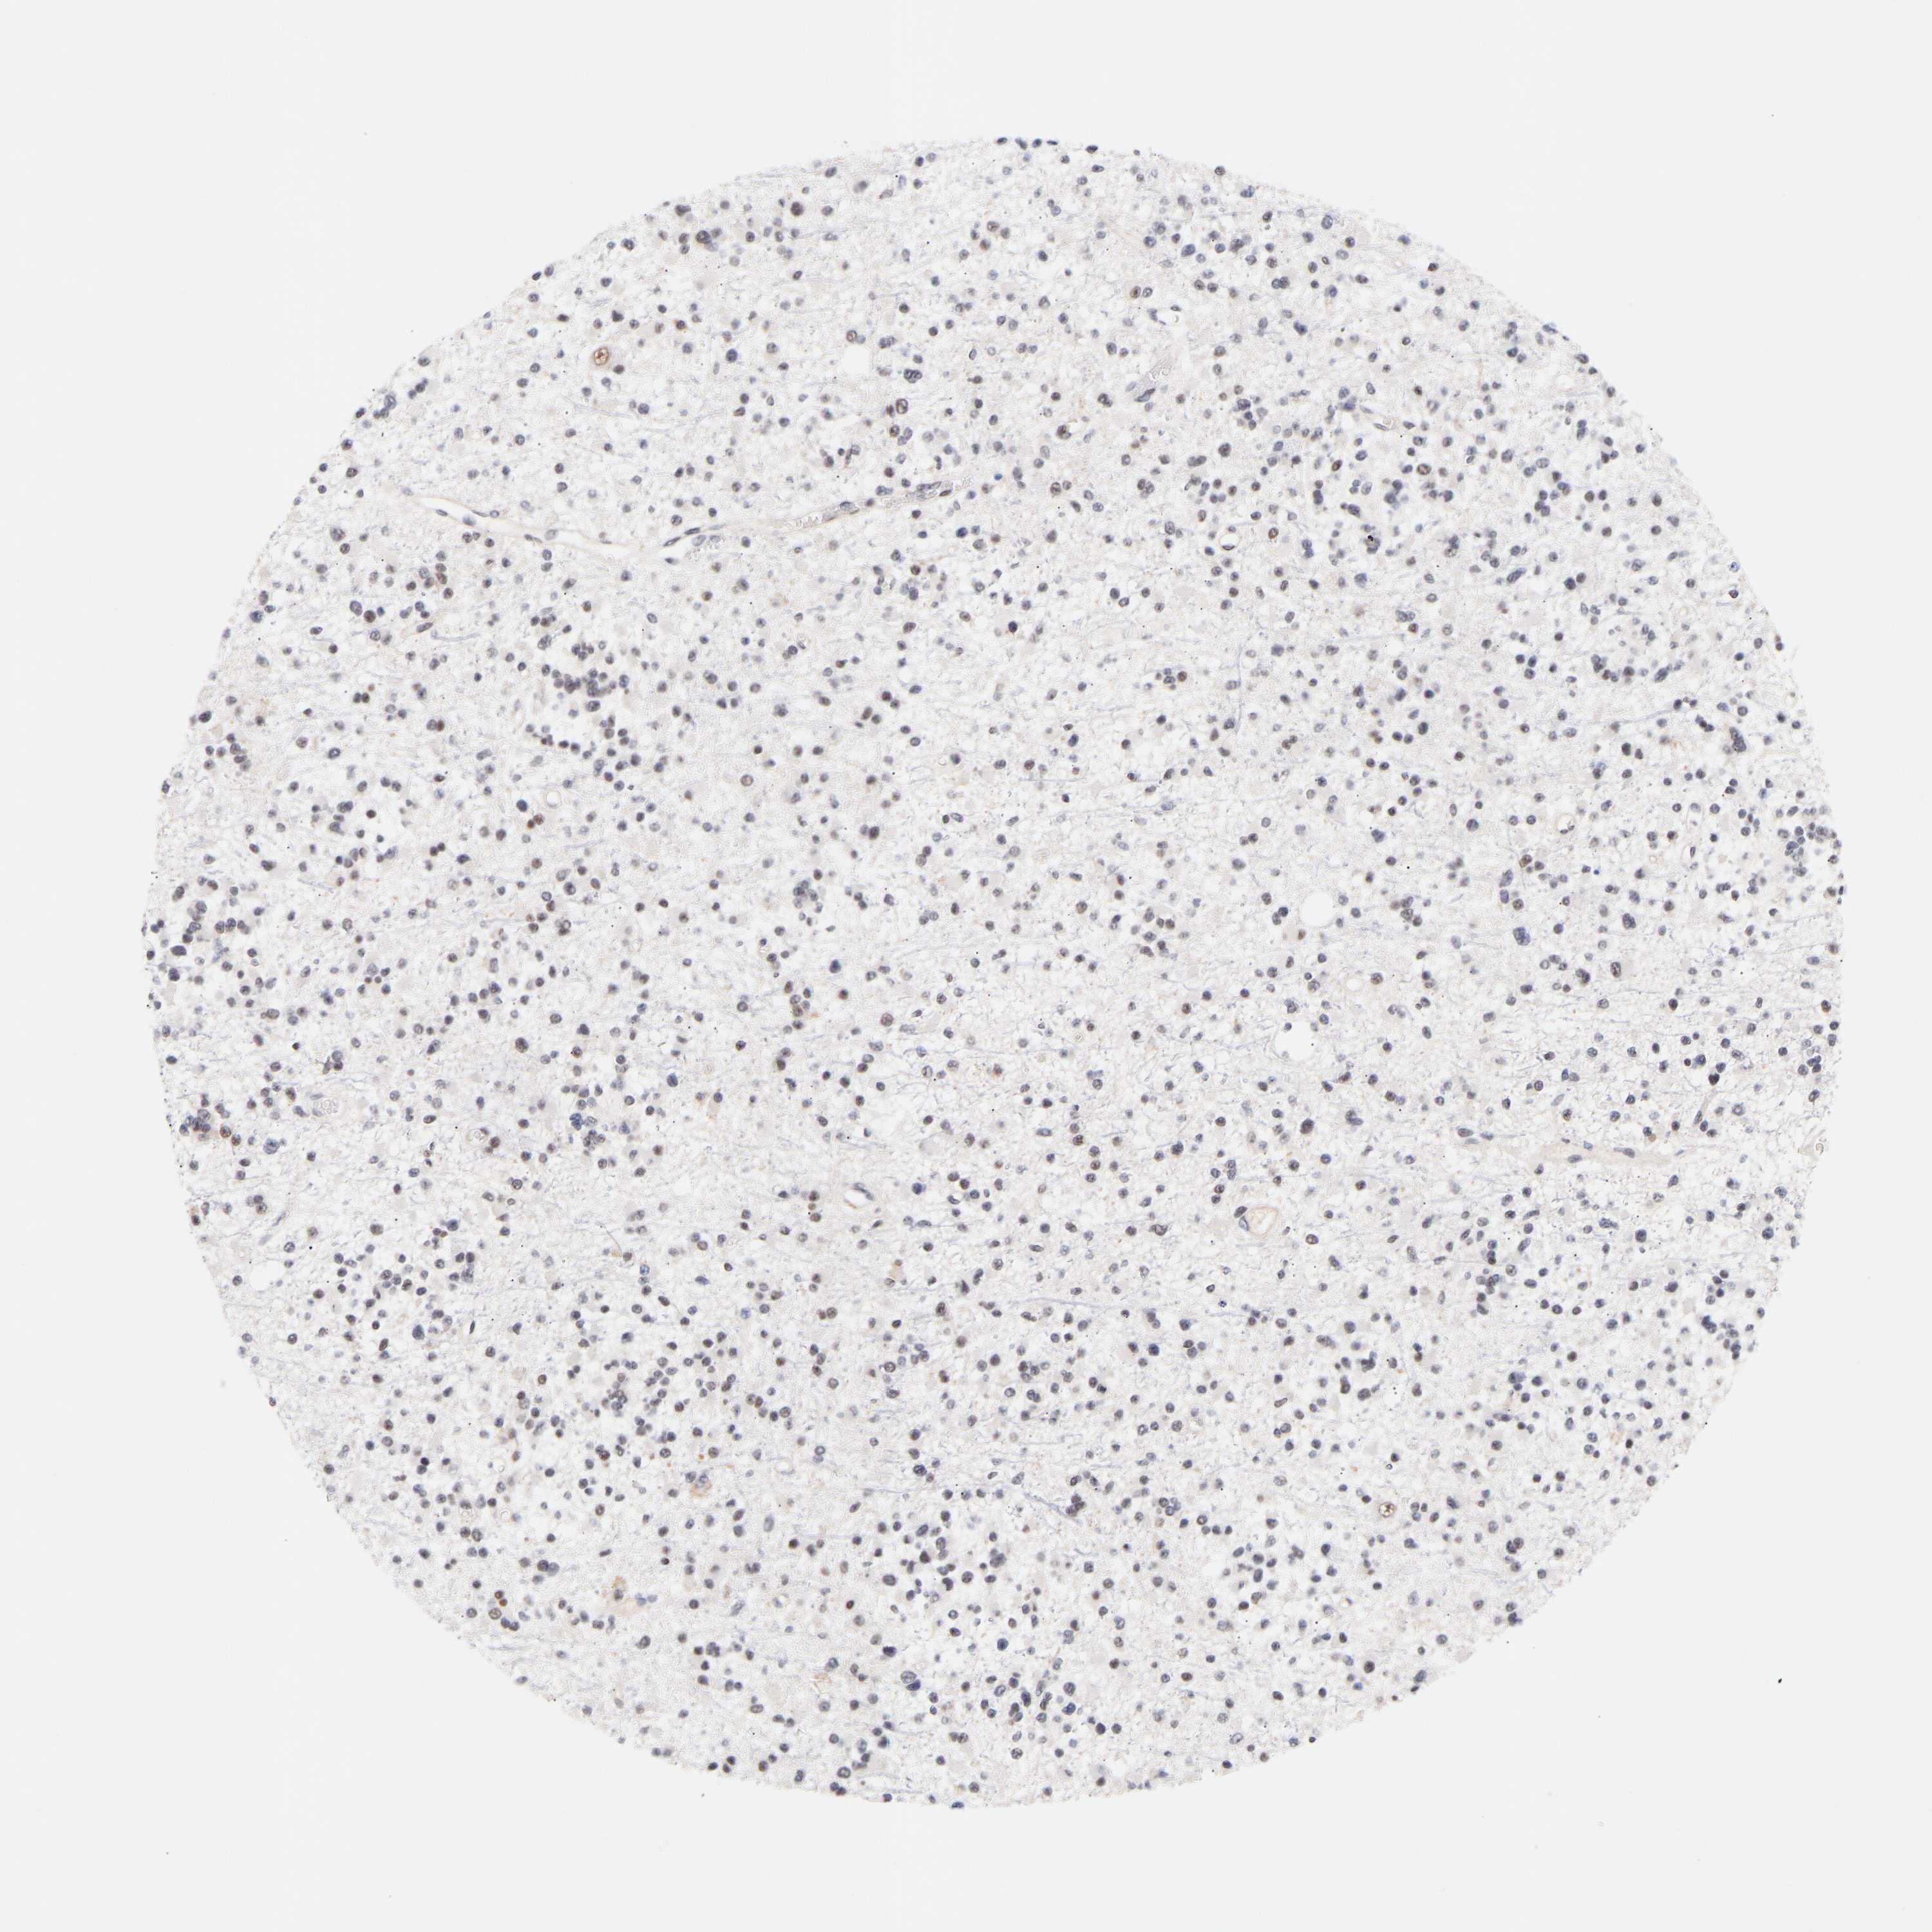

GLIOMA - Protein expressioni

A mouse-over function shows sample information and annotation data. Click on an image to view it in a full screen mode. Samples can be filtered based on level of antibody staining by selecting one or several of the following categories: high, medium, low and not detected. The assay and annotation is described here.

Note that samples used for immunohistochemistry by the Human Protein Atlas do not correspond to samples in the TCGA dataset.

Antibody stainingi

Antibody staining in the annotated cell types in the current human tissue is reported as not detected, low, medium, or high, based on conventional immunohistochemistry profiling in selected tissues. This score is based on the combination of the staining intensity and fraction of stained cells.

Each image is clickable and will lead to virtual microscopy that enables deeper exploration of all samples and also displays staining intensity scores, fraction scores and subcellular localization as well as patient and tissue information for each sample.

Antibody HPA019824

Antibody CAB015201

Staining

High

Medium

Low

Not detected

Intensity

Strong

Moderate

Weak

Negative

Quantity

>75%

75%-25%

<25%

None

Location

Nuclear

Cytoplasmic/membranous

Cytoplasmic/membranous,nuclear

Glioma, malignant, High grade

Glioma, malignant, Low grade